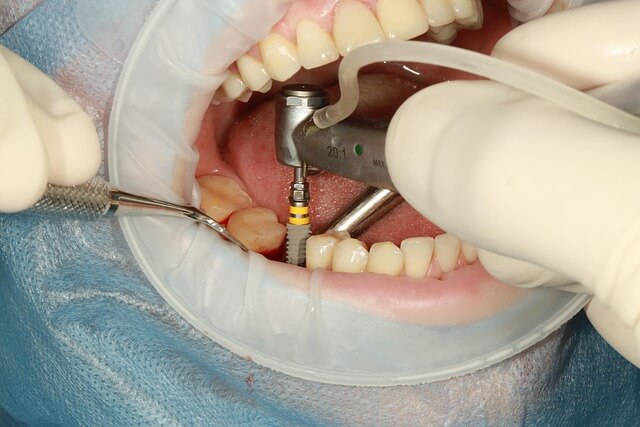

* 65세이상 노인 의료 혜택 중 또 하나 주목할 부분은 치과 치료 지원입니다. 건강보험이 적용돼 틀니, 임플란트 본인 부담금이 30%로 줄었습니다. 최대 4개까지 지원 가능하며, 의료급여 수급자는 10% 부담입니다. 가까운 치과 방문 시 검진과 함께 신청할 수 있어 편리합니다.

65세이상 노인 의료 혜택에 대해 제가 직접 경험한 내용을 바탕으로 말씀드리겠습니다. 저희 부모님이 만 65세를 넘어서면서 적용받은 가장 큰 혜택은 틀니 및 임플란트 비용 지원입니다. 건강보험 적용으로 실제 비용 부담이 크게 줄었고, 최대 2개의 임플란트에 대해 70%가 지원되니 경제적 부담이 상당히 덜해졌습니다. 이외에도 골다공증 검사, 치매 조기검진 등 예방적 건강검진이 무료로 제공되어 건강관리 부담 완화에 큰 도움이 되죠.

제가 직접 경험한 바에 의하면, 65세이상 노인 치과의료 혜택은 건강보험에서 틀니부터 임플란트까지 폭넓게 지원합니다. 특히, 치아 상실로 고생하던 어르신들에게 좋은 소식입니다. 임플란트는 최대 2개까지 건강보험 혜택이 적용되어 본인 부담금이 30% 정도에 불과합니다.

신청 절차와 팁

- 가까운 보건소나 치과에서 건강보험 적용 여부 확인 및 상담

- 기본 진료 후 건강보험 지원 대상자 확인

- 신청서 제출 후 틀니·임플란트 시술 예약 진행

저도 어머님의 임플란트 시술 시 이 절차를 직접 도와드렸는데, 미리 상담만 잘 받고 진행하면 꼼꼼한 혜택 챙기기가 가능합니다. 65세이상 노인 치과의료 혜택 궁금한 점은 관련 사이트나 보건소에 문의하면 친절하게 안내해줍니다.

| 틀니 및 임플란트 | 건강보험 적용, 최대 2개 임플란트 70% 지원 | 만 65세 이상 건강보험 가입자 | 본인 부담금 약 30% |

치과 임플란트 지원은 몇 개까지 가능한가요?

최대 2개까지 건강보험에서 70% 지원받을 수 있습니다.

- 의료비 지원: 치과 치료(틀니, 임플란트)의 본인 부담률을 30%로 낮추고, 건강보험이 적용되어 경제적 부담이 크게 줄어듭니다.

실제로 체감한 65세이상 노인 의료 혜택의 가치

제가 직접 경험한 65세이상 노인 의료 혜택 중 가장 큰 변화는 틀니 및 임플란트 지원 덕분에 가족들이 경제적 부담 없이 치과 치료를 받을 수 있었다는 점입니다. 본인부담률 30% 제도 적용으로 고액의 치과 치료비를 절감할 수 있었고, 품질 좋은 치료를 받으며 건강한 구강 상태를 유지할 수 있었습니다.

- 치과 치료 지원은 건강보험증을 지참하여 지정 치과에서 진료받을 것